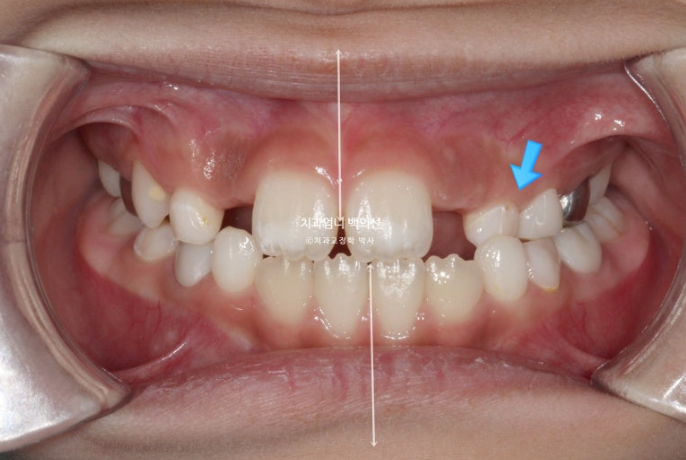

중심선이 많이 어긋나 있으며 파란화살표는 위아래가 거꾸로 물리는 반대교합입니다.

노란색 아래턱의 중심, 흰색이 윗턱의 중심선입니다.

아래턱이 치아중심선 만큼 왼쪽으로 틀어진 비대칭입니다.

유치송곳니끼리 거꾸로 물리는 상태라 이 부분에 교합간섭이 있습니다.

교합간섭에 의해 턱을 한쪽으로 틀어서 물게 되는 경우가 있습니다.

이 경우 악궁확장으로 거꾸로 물리는 부분, 즉 교합간섭을 해결해주면 비대칭이 자연스럽게 좋아지기도 합니다.